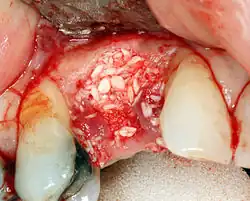

Bone loss (peri-implantitis) on implants over 7 years in a heavy smoker

Cement peri-implantitis

Dental cement under the gingiva causes peri-implantitis and implant failure.

Beyond the possibility of mechanical failure[98] which may be due to poor prosthetic fitment, wear and tear, or user-induced actions such as bruxism, dental implants are also subject to peri-implant mucositis and peri-implantitis, where gum tissue and bone mass around the implant are resorbed, and the implant gradually becomes loose, and has to be removed.[99][100] In addition, although titanium is generally well tolerated by the body, there have been cases where the build-up of titanium particles released by the implant may cause systemic inflammatory response.[101] Because there is no dental enamel on an implant, it does not fail due to cavities like natural teeth. While large-scale, long-term studies are scarce, several systematic reviews estimate the long-term (five to ten years) survival of dental implants at 93–98 percent depending on their clinical use.[15][16][17] During initial development of implant retained teeth, all crowns were attached to the teeth with screws, but more recent advancements have allowed placement of crowns on the abutments with dental cement (akin to placing a crown on a tooth). This has created the potential for cement, that escapes from under the crown during cementation to get caught in the gingiva and create a peri-implantitis (see picture below). While the complication can occur, there does not appear to be any additional peri-implantitis in cement-retained crowns compared to screw-retained crowns overall.[102] In compound implants (two stage implants), between the actual implant and the superstructure (abutment) are gaps and cavities into which bacteria can penetrate from the oral cavity. Later these bacteria will return into the adjacent tissue and can cause periimplantitis.